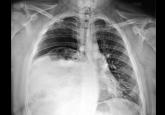

ArticleEventration of the diaphragm presenting as spontaneous pneumothoraxAuthor:Pauline Go, MDPublish date: January 1, 2016A 25-year-old man presents with the sudden onset of right-sided back and chest pain and shortness of breath.Read More